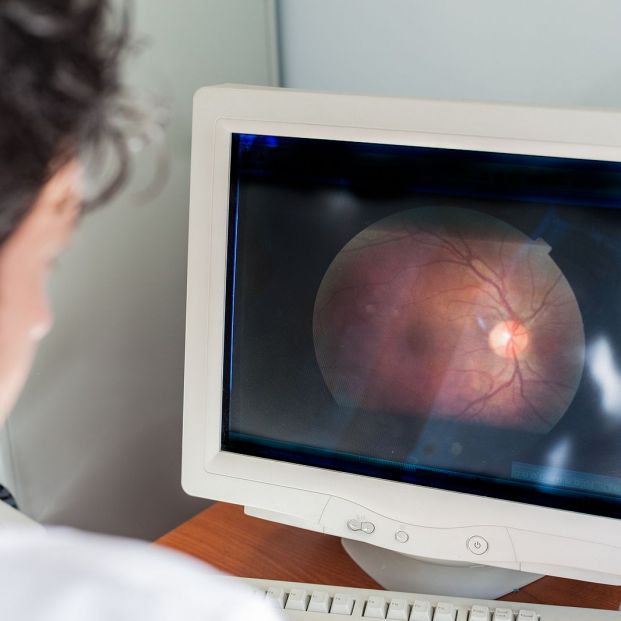

Y ha insistido: "El ojo es un sustituto del cerebro, y este estudio demuestra que la infección bacteriana retiniana y la inflamación crónica pueden reflejar la patología cerebral y predecir el estado de la enfermedad, lo que respalda la imagenología retiniana como un método no invasivo para identificar a las personas con riesgo de padecerla".

Para realizar el estudio, los investigadores utilizaron imágenes avanzadas, pruebas genéticas y análisis de proteínas para examinar el tejido retiniano de 104 personas, algunas con cognición normal, algunas con deterioro cognitivo leve y otras con enfermedad de Alzheimer.

Los hallazgos sugieren que abordar la infección bacteriana crónica y la inflamación que desencadena podría representar una nueva estrategia de tratamiento. La investigación también respalda el posible uso de la retina como método no invasivo para diagnosticar y monitorear la enfermedad.